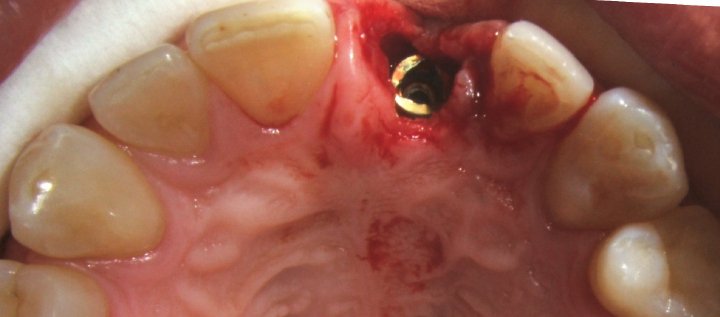

Healing Screw On The Impant

Immediate Implant Placement

Removal Of Tooth